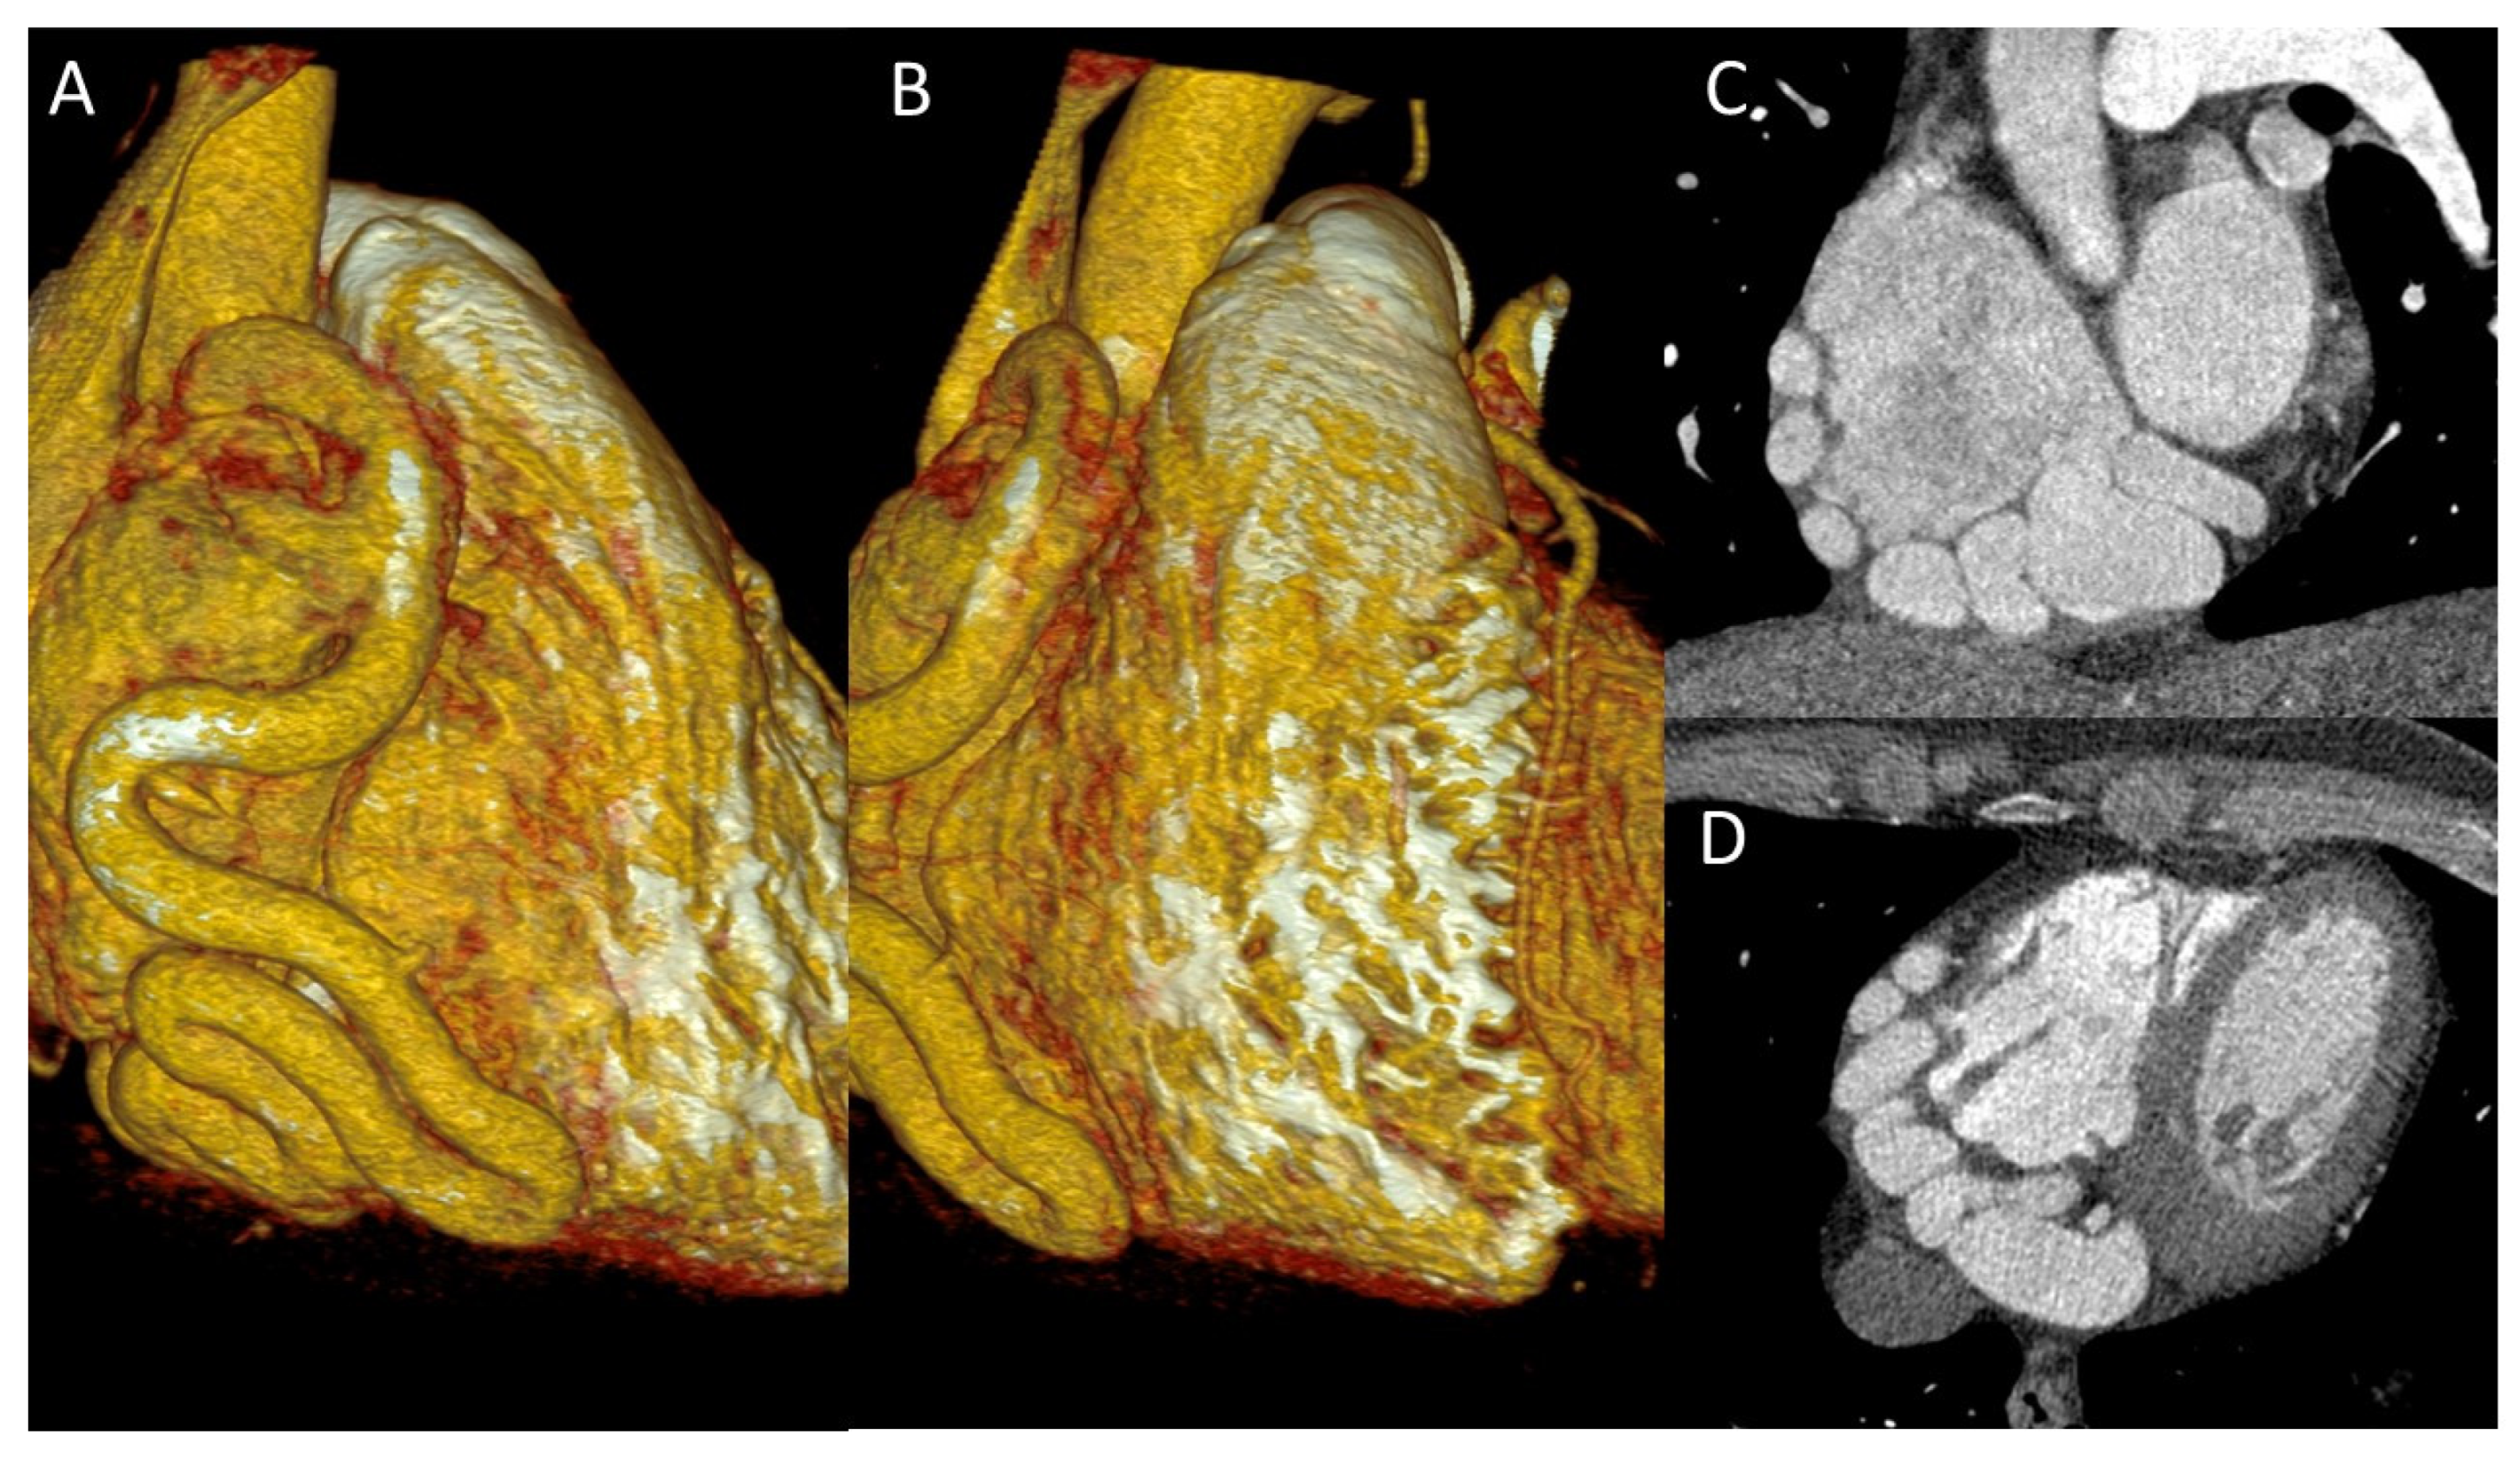

Figure 8. Coronary arteriovenous fistula: Circumflex Artery draining Directly into the Coronary Sinus. (A,B) Three-dimensional volume-rendered image showing the circumflex artery giving rise to an arteriovenous fistula draining directly into the coronary sinus. (C,D) CCTA image demonstrating the course of the circumflex artery–to–coronary sinus fistulous connection.

Termination anomalies include coronary artery fistulas (CAF) and coronary stenosis. Coronary artery fistulas are defined by an abnormal communication between the coronary artery and a heart chamber (most commonly being the right ones), the coronary sinus, a great vessel or other vascular structure. They affect 0.1 to 0.2 % of the population, and most of the time they are asymptomatic (class II Rigatelli). 90% of CAFs drain into the right heart chambers but drainage into the left heart chambers is also possible.

Among the possible complications, CAFs can cause a coronary steal phenomenon, leading to progressive dilatation and tortuosity of the affected vessel. This dilatation can be self-sustaining resulting in giant CAFs (> 8mm diameter), tortuous and polyangular coronary arteries. One or multiple may be present in a single patient. Potential complications include thrombosis, stenosis, myocardial ischemia, ventricular dysfunction, rupture, heart failure, and even cardiogenic shock.

Clinically, the presentation varies with age: in newborns, it typically manifests as heart failure, whereas in adults, the clinical picture is more often that of myocardial ischemia, SCD, pulmonary hypertension, heart failure, arrhythmia, rupture, or endocarditis- symptoms that will most commonly appear in the fifth or sixth decade of life (5,19,31). (Figure 7)